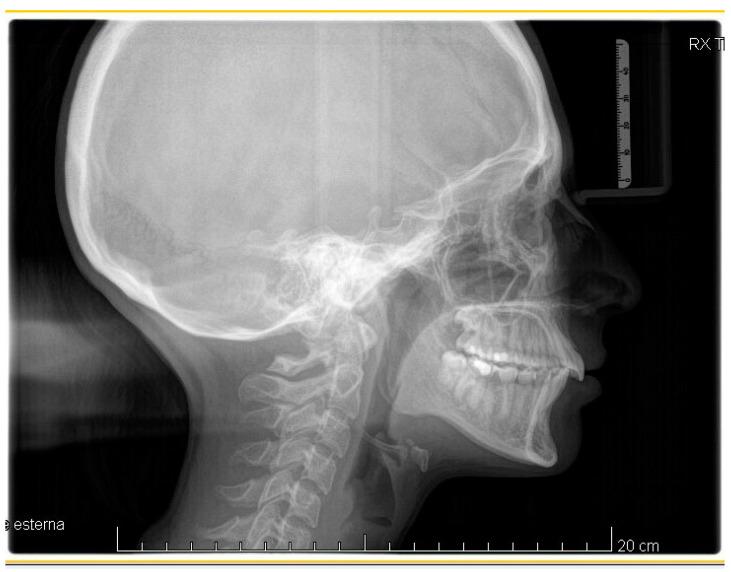

Successful closure of edentulous spaces with clear aligners (CAs) is influenced by many factors. CAs are tailored orthodontic devices whose predictability may have relevant medico-legal implications. This study presents a scoping review about missing molar space closure (MMSC) with CAs and a clinical case. This study aims to highlight the feasibility of molar space closure by mesialization with CAs without hybrid supports. Following PRISMA Sc-review guidelines, English-written randomized/non-randomized/observational clinical studies on PubMed, Scopus, Cochrane and Lilacs were searched. An 18-year-old patient, with upper and lower edentulous spaces due to the loss of two first molars, was rehabilitated with CAs (Sorridi, Sorridi srl, Latina, Italy) without hybrid supports and attachments. The therapy was carried out over 10 months. Currently, there are no studies documenting MMSC by mesialization with only CAs. Existing articles document the closure of premolar or incisor spaces. The upper and lower left second molars replaced the missing first molars, and erupting third molars replaced adjacent teeth. The biomechanical effects in space closure with CAs related to extraction cases appear as priorities of clinical/medico-legal interest. Our case turns attention to this movement of CAs without attachments/hybrid supports, indicating that even such a complex treatment can be comfortable for patients and safely predictable for specialists.

使用透明矫治器(CA)成功关闭无牙间隙受多种因素影响。CA是定制的正畸装置,其可预测性可能具有相关的医疗法律意义。本研究呈现了一项关于使用CA关闭缺失磨牙间隙(MMSC)的范围综述及一个临床病例。本研究旨在强调在无混合支持的情况下通过CA近中移动关闭磨牙间隙的可行性。遵循PRISMA范围综述指南,检索了PubMed、Scopus、Cochrane和Lilacs上英文撰写的随机/非随机/观察性临床研究。一名18岁患者因两颗第一磨牙缺失导致上下无牙间隙,使用CA(Sorridi,Sorridi srl,拉蒂纳,意大利)进行修复,无混合支持和附件。治疗持续了10个月。目前,尚无研究记录仅通过CA近中移动关闭MMSC的情况。现有文章记录了前磨牙或切牙间隙的关闭。上下颌左侧第二磨牙替代了缺失的第一磨牙,萌出的第三磨牙替代了相邻牙齿。与拔牙病例相关的CA关闭间隙的生物力学效应似乎是临床/医疗法律关注的重点。我们的病例将注意力转向了无附件/混合支持的CA这种移动方式,表明即使是如此复杂的治疗对患者来说也可以是舒适的,对专家来说也可以是安全可预测的。